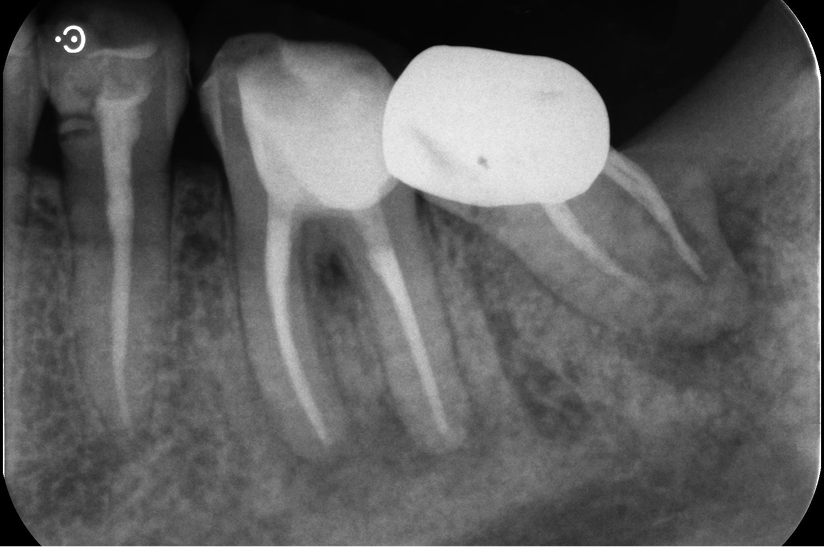

自家歯牙移植と根管治療で

天然歯を保存した症例

タップで写真の拡大ができます。

Before

Under Treatment

After

主訴

歯を残せないと言われた。インプラントは先延ばしにしたい

治療内容

自家歯牙移植 / イニシャルトリートメント(大臼歯)レジンコア

治療期間

2ヶ月

治療費用

308,000

治療の

リスク

術後しばらくしてから骨性癒着、外部吸収を起こす可能性があります。